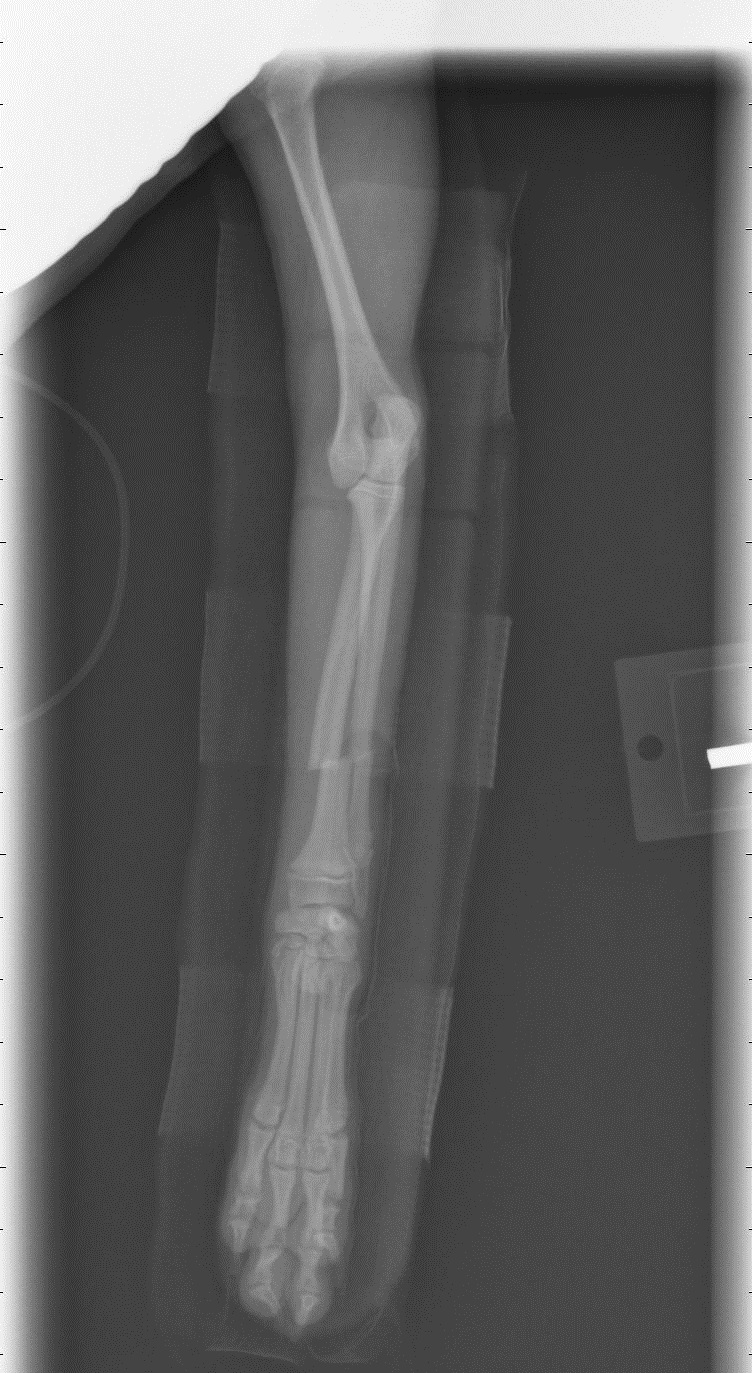

Щенок той-пуделя, 5 месяцев, вес 1.5 кг, прыгнула с высоты меньше метра и получила закрытый перелом обеих лучевых костей на передней лапе. У ветеринара мы были уже через полчаса. Ветеринар наложил лангету, но на снимке кости не совмещены идеально. Кости настолько маленькие, что без операции, думаю, лучше совместить их не удастся. По словам ветеринара, такого совмещения должно быть достаточно, чтоб кости срослись, и операцию можно не делать. Я понимаю, что он профессионал, но мне до этого доводилось иметь дело с некомпетентными ветеринарами (не этим), так что хочется услышать мнения. Делать операцию и мучить собаку еще одним наркозом, или надеяться, что заживет и так? Если можно, пишите, ветеринар вы, или просто владелец.

Я так понял, что ветеринар, который ставил гипс, либо не умеет делать такие операции, либо у них в клинике нет для этого оборудования (что странно, так как это что-то вроде круглосуточного ветеринарного травм-пункта). Поэтому не знаю, какой ему был резон так говорить. Есть опасения, что в других клиниках тут же начнут продавать свои услуги по операции, даже если она не нужна.

Вот снимки. Первый до, второй и третий после. Спасибо.

Sabut, Да, такой перелом без остеосинтеза - накостного (пластина) или внутримедуллярного (спица) - трудно иммобилизовать. Так как нога сейчас сложена - кости скорее всего срастутся если нога неподвижна, но лапа останется коротковатой и кривоватой. С другой стороны, делать остеосинтез собаке в полтора кг весом - трюк ещё тот... должен делать оч. хороший специалист (Вы где территориально?).

Также, чем кормите собачку? Либо она очень неудачно прыгнула, либо слишком хрупкие кости, что бывает связано с рационом или генетическое.

Все более убеждаюсь в третьем подряд опыте некомпетентного ветеринара. Я запостил этот вопрос на несколько форумов. Все в один голос твердят, что так оставлять нельзя. Послал фотки местному ортопеду - тот же ответ. Назначили операцию на завтра.